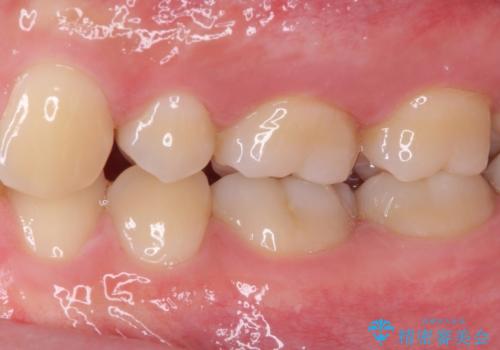

神経近くにまで及んだ大きなむし歯のセラミッククラウン

- 下顎左右奥歯に虫歯で痛みを感じるとのことで来院された患者様です。

むし歯が大きく、神経を取り除く可能性があることを理解いただいた上で虫歯を取り除き、その後はオールセラミッククラウンにて補綴することとしました。

虫歯除去後に痛みは収まり、神経も保存することができました。

変色していた歯もセラミッククラウンで自然な色合いとなり、患者様には大変満足していただきました。